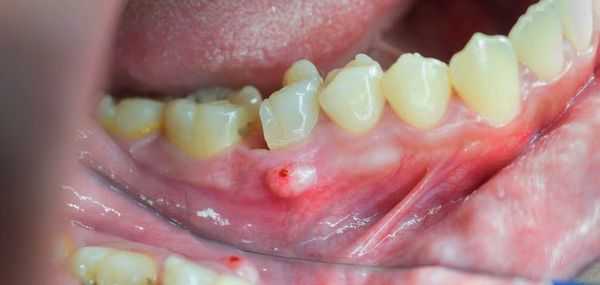

После острой стадии наступает подострая. На десне образуется гнойничок или свищ, через который гнойные выделения и воспалительная жидкость выходят наружу.

![Свищ на десне]()